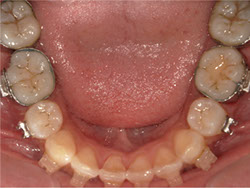

1期治療でスケルトンタイプの拡大装置で歯列拡大後、上下第一小臼歯を抜歯して口元もキレイになりました。

矯正前